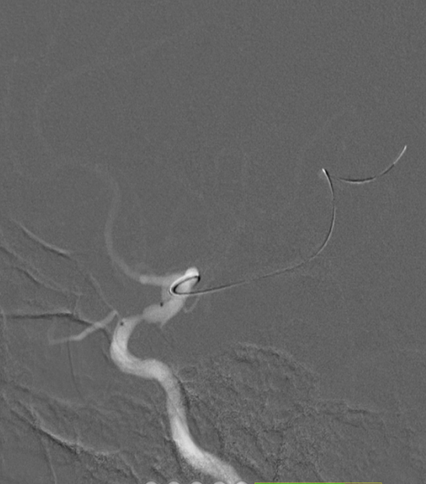

导丝怎么扩【载药时代 球扩天下】NOVA DES®颅内药物洗脱支架在颈内动脉颅内段重度狭窄中的应用体会二例!_https://www.jmylbn.com_新闻资讯_第29张

支架释放

术后影像及检查

影像结论:术后残余狭窄小于 10%。